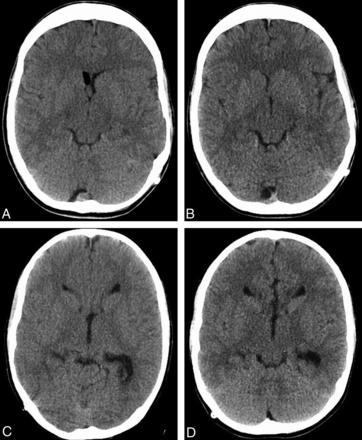

Our findings of a 22% reduction in the average CTDIvol and a 24% reduction in the average DLP when using 20% ASIR, at no significant detriment to subjective image quality, are consistent with the prior published results performed in adults (Fig 4). Kilic et al21 consecutively performed nonenhanced head CT scans in 149 patients; the first 51 patients underwent their original FBP protocol, and the remaining 98 patients underwent their lower-dose IR protocol reconstructed at 30% ASIR. The group reported a 31% decrease in the average DLP of their ASIR studies, without a significant change in image quality or interpretability. The study published by Korn et al22 involved 90 adult patients undergoing nonenhanced and enhanced CT of the brain who were randomized to be scanned with either their original head CT FBP protocol or with 1 of 2 low-dose IR protocols. All of these examinations were then subsequently reconstructed with both FBP and IRIS and compared. The authors found that a 15% dose reduction did not impact subjective or objective image quality when the images were reconstructed with IRIS but that a 30% dose reduction resulted in noticeable degradation of image quality when reconstructed with IRIS.

Examples of study patients. Images from FBP (A) and ASIR (B) examinations performed 26 days apart in a 14-year-old patient, with a 23.7% decrease in the CTDI (34.9–27.5 mGy) and a 39.6% decrease in the DLP (581.5–389.3 mGy-cm) in the latter examination. Images from FBP (C) and ASIR (D) examinations performed 77 days apart in a 10-year-old patient, with a 26.4% decrease in the CTDI (32.3 to 24.7 mGy) and a 25.8% decrease in the DLP (452.3 to 349.0 mGy-cm) in the latter examination.